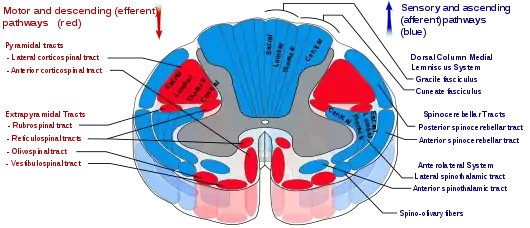

The reticular formation is a set of interconnected nuclei that are located throughout the brainstem. It is not anatomically well defined, because it includes neurons located in different parts of the brain. The neurons of the reticular formation make up a complex set of networks in the core of the brainstem that extend from the upper part of the midbrain to the lower part of the medulla oblongata.[2] The reticular formation includes ascending pathways to the cortex in the ascending reticular activating system (ARAS) and descending pathways to the spinal cord via the reticulospinal tracts.[3][4][5][6]

The reticulospinal tracts, also known as the descending or anterior reticulospinal tracts, are extrapyramidal motor tracts that descend from the reticular formation[40] in two tracts to act on the motor neurons supplying the trunk and proximal limb flexors and extensors. The reticulospinal tracts are involved mainly in locomotion and postural control, although they do have other functions as well.[41] The descending reticulospinal tracts are one of four major cortical pathways to the spinal cord for musculoskeletal activity. The reticulospinal tracts work with the other three pathways to give a coordinated control of movement, including delicate manipulations.[40] The four pathways can be grouped into two main system pathways – a medial system and a lateral system. The medial system includes the reticulospinal pathway and the vestibulospinal pathway, and this system provides control of posture. The corticospinal and the rubrospinal tract pathways belong to the lateral system which provides fine control of movement.[40]

This descending tract is divided into two parts, the medial (or pontine) and lateral (or medullary) reticulospinal tracts (MRST and LRST).

- The medial reticulospinal tract is responsible for exciting anti-gravity, extensor muscles. The fibers of this tract arise from the caudal pontine reticular nucleus and the oral pontine reticular nucleus and project to lamina VII and lamina VIII of the spinal cord.

- The lateral reticulospinal tract is responsible for inhibiting excitatory axial extensor muscles of movement. It is also responsible for automatic breathing. The fibers of this tract arise from the medullary reticular formation, mostly from the gigantocellular nucleus, and descend the length of the spinal cord in the anterior part of the lateral column. The tract terminates in lamina VII mostly with some fibers terminating in lamina IX of the spinal cord.